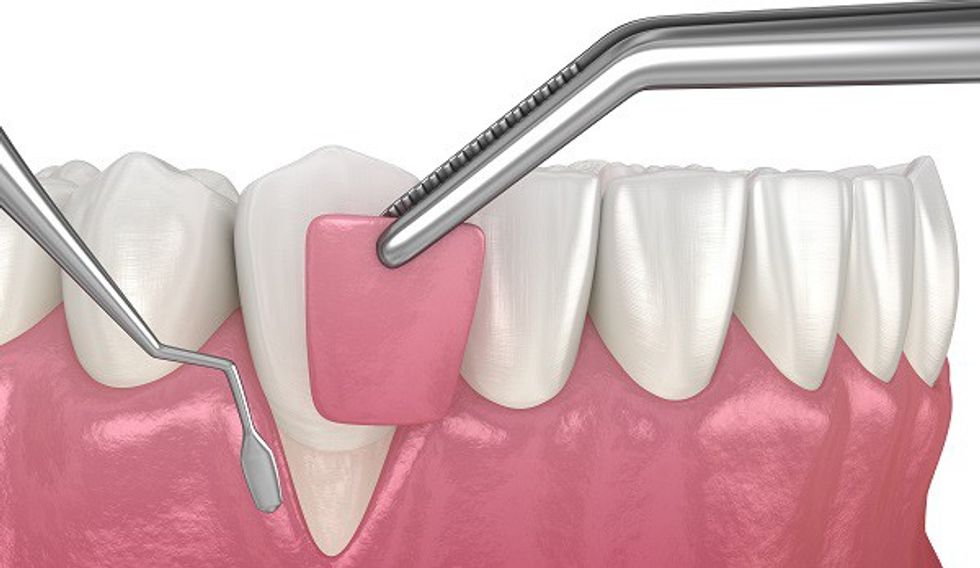

Graftimi i gingivës (mishrave të dhëmbëve) është një procedurë dentare për trajtimin e hollimit të mishrave të dhëmbëve ose recesionit (tërheqjes) së mishrave të dhëmbëve. Kjo procedurë zëvendëson indin e humbur rreth dhëmbëve tuaj dhe përmirëson shëndetin tuaj të përgjithshëm oral.

Graftimi i gingivës mbulon rrënjët e ekspozuara të dhëmbëve dhe i shton vëllim mishrave të dhëmbëve, duke përmirësuar shëndetin e përgjithshëm oral.

Rikonkstruksioni i recesioneve gingivale me grafte gingivale është një procedurë që ndihmon në rivendosjen e mishrave të dhëmbëve që janë tërhequr.